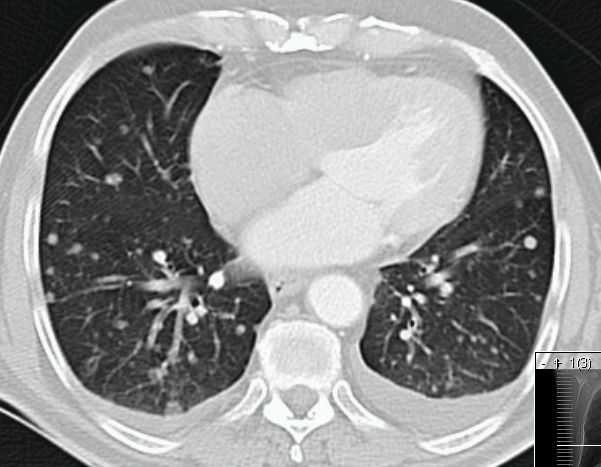

Lungenmetastasen.![]() |